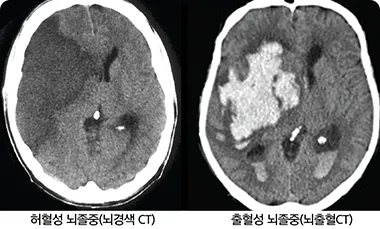

뇌혈관이 파열된 상태를 말하는 뇌출혈과 혈관이 막힌 뇌경색으로 크게 구분됩니다.

출혈성 뇌졸중 (뇌출혈) : 뇌혈관이 터져 피가 새어나가는 상태입니다.

허혈성 뇌졸중 (뇌경색): 뇌 내부 혹은 뇌로 향하는 혈관이 막혀 특정 부위에 혈액 공급이 중단되는 상황을 말합니다.

- CT 검사 : 뇌를 빠른 시간 내에 검사하여 출혈이나 뇌 조직의 손상을 쉽게 확인할 수 있습니다.